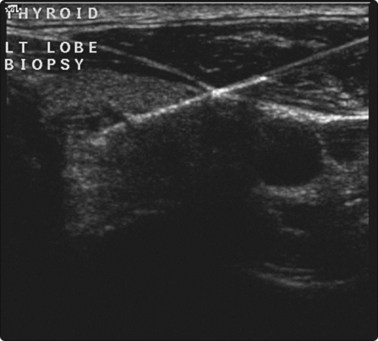

image

Fig. 3.12 Thyroid biopsy

Aspirate is visible in the needle, and is seen to move during aspiration.